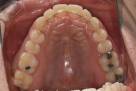

치료 전

치료 후

[덧니_비발치]

전체교정 (20대 남성)